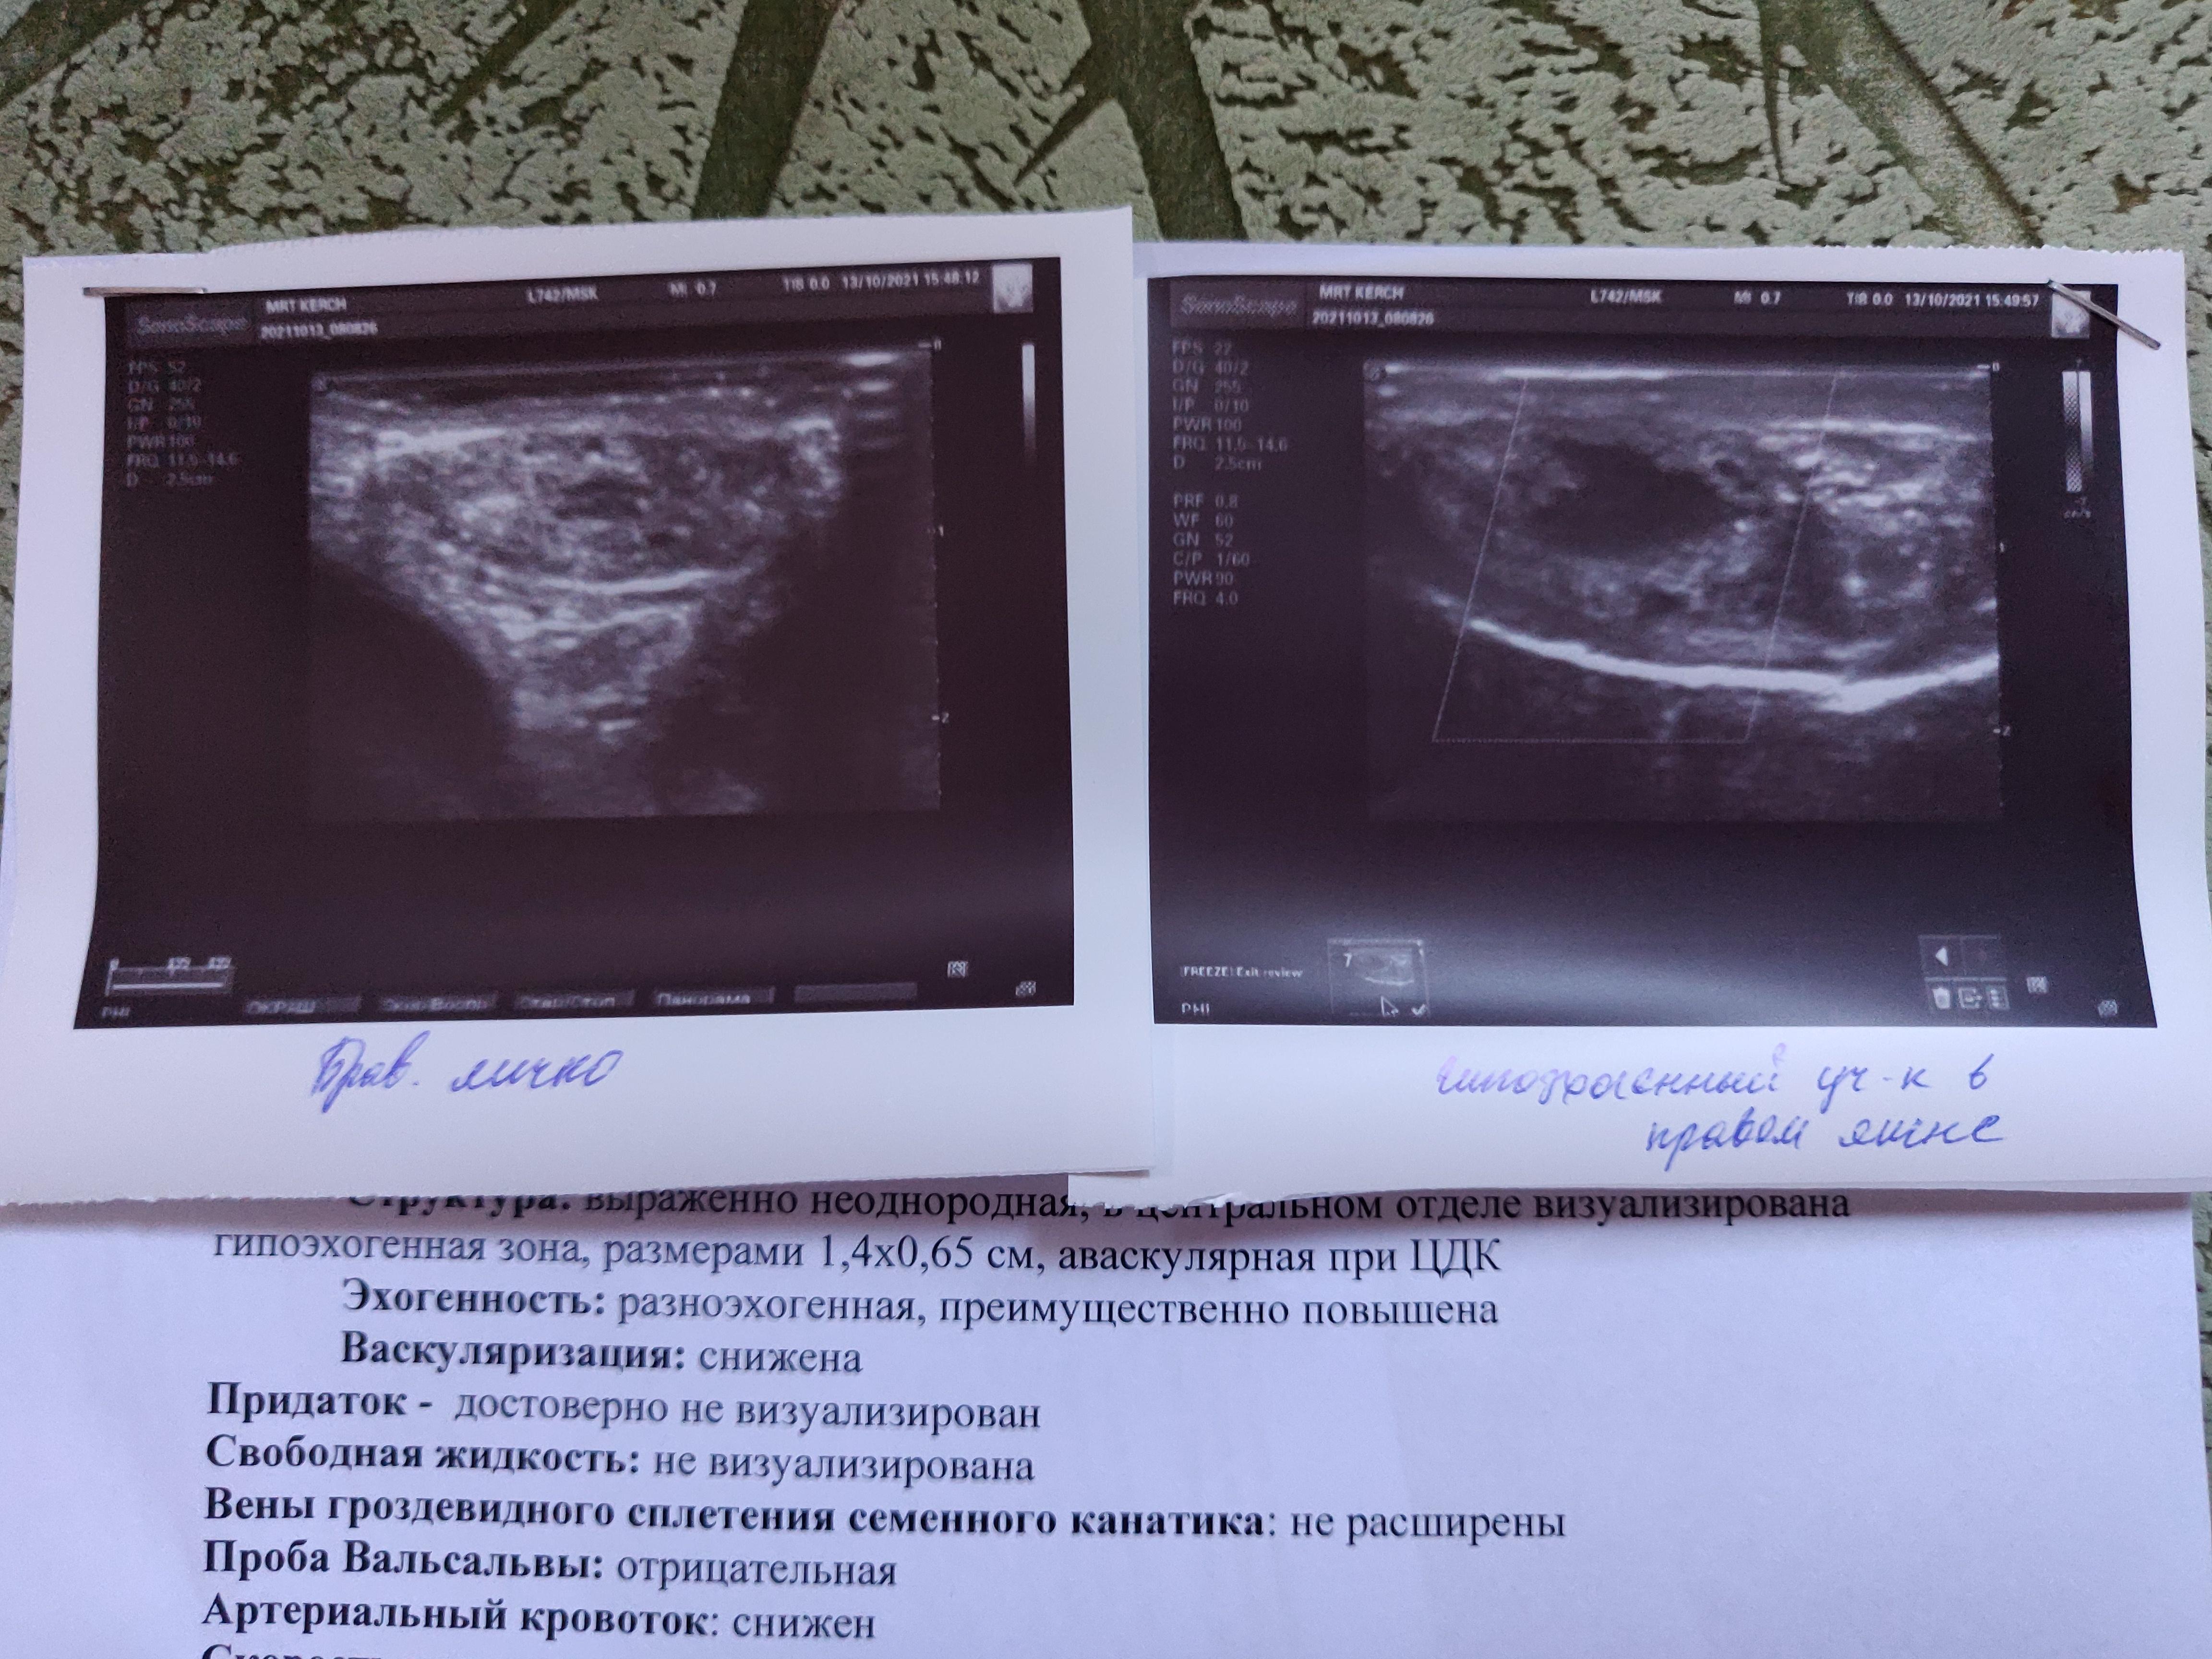

У мужчины 26 лет. Крипторхизм справа. Не оперирован. Знаю, что такие операции делаются ещё в детстве. Было поздно обнаружено, почти в подростковом возрасте. Врачи ввели в заблуждение словами, что ничего делать не нужно. В итоге, одно яичко не развито. Находится в нижней части пахового канала. Гипоплазия. Из симптомов, иногда возникают неприятные ощущения, в этой области выпячивание небольшое в районе лобка. В 12 ЛЕТ БЫЛА ОПЕРИРОВАНА ПАХОВАЯ ГРЫЖА. Я так понимаю, яичко необходимо удалить. Вопрос в следующем.

Прикрепляю УЗИ с фото образования, по нему нашли включение без кровотока. Насколько вероятно это опухоль? Достаточно ли сдать онкомаркеры АФП, ХГЧ и ЛДГ? Для исключения опухоли. Что такое микрокальцинаты? Опасны ли они в здоровом яичке?

Какая дальнейшая тактика обследования и прогноз? Смертельно ли это опасно, может ли мужчина быть полноценным? Большое спасибо за ответы. Вопрос задаю, потому что не могу найти себе места уже. Есть ли вероятность, что это не рак?! (УЗИ прикрепила недавнее с доплером с фото и старое УЗИ прошлого года, но оно мало информативное без доплерографии).